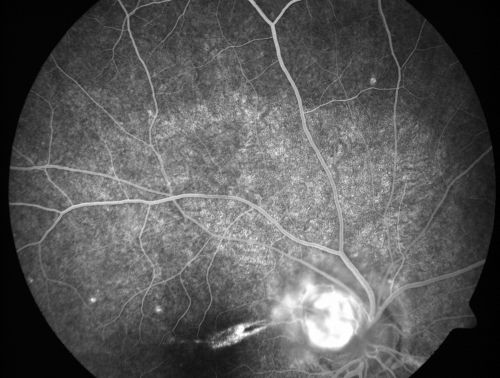

Toxocariasis

15-year-old one year ago had pink eye then her vision has been abnormal. She recently went for a drivers’ test and failed, OD: 20/80; OS: 20/20.